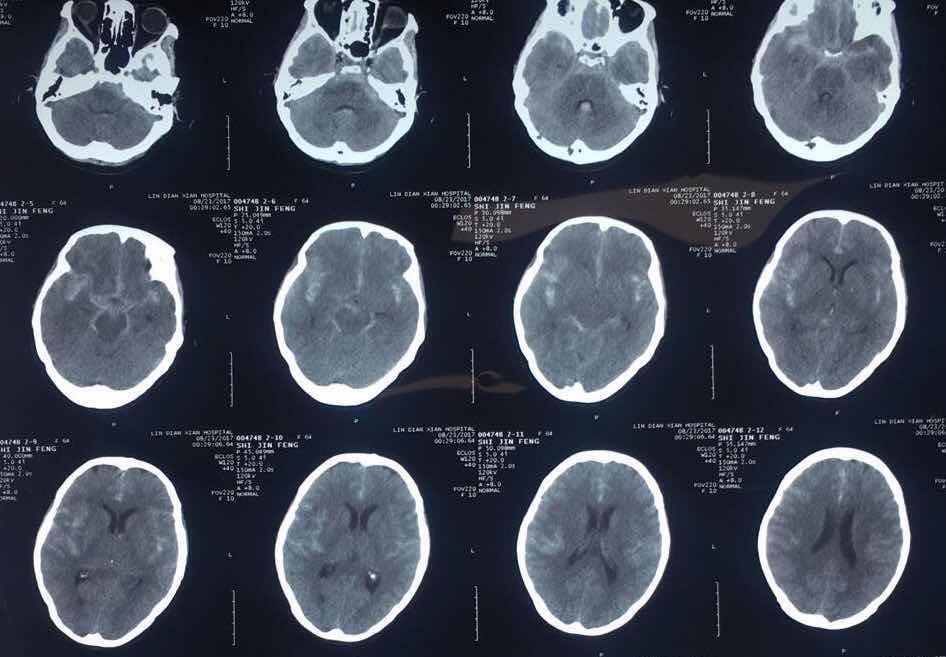

术前头部CT

8月22日对于石大娘及家人来说是不幸的,当天夜里石大娘在睡觉过程中出现憋气,被家人发现意识不清及小便失禁,随即被家人送到附近医院,做头CT检查,发现“蛛网膜下腔出血”,并且出血量大,为求进一步诊治,23日早上120转送至我院,神经外二科值班医生接诊后,结合患者病史,高度怀疑为颅内动脉瘤、动静脉畸形破裂,立即给予止血、降血压、抗血管痉挛等治疗。

颅内动脉瘤被称为颅内的“不定时炸弹”,随时有再次破裂出血可能,一旦出血预后极差。患者属于亨-汉氏分级3级,急诊全脑脑血管造影显示患者为颅内多发动脉瘤,一枚位于右侧大脑中动脉M3段,一枚位于左侧大脑前动脉A1段。两枚动脉瘤相当于两枚“不定时炸弹”,其危险程度可想而知,而且术前难以判断责任动脉瘤。